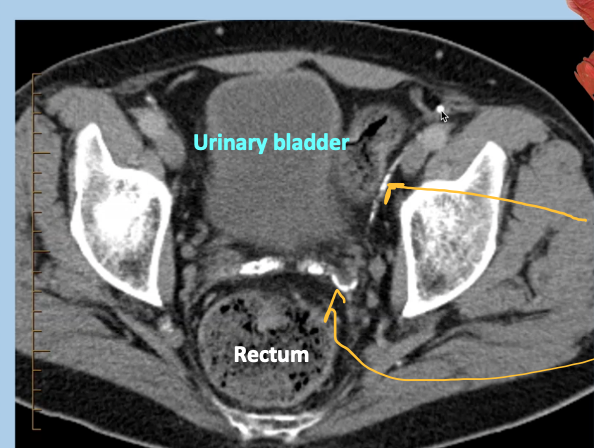

CT pelvis